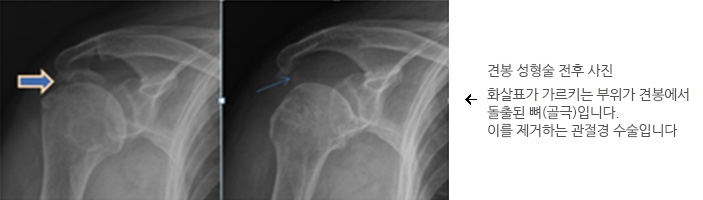

- 충돌증후군

충돌증후군